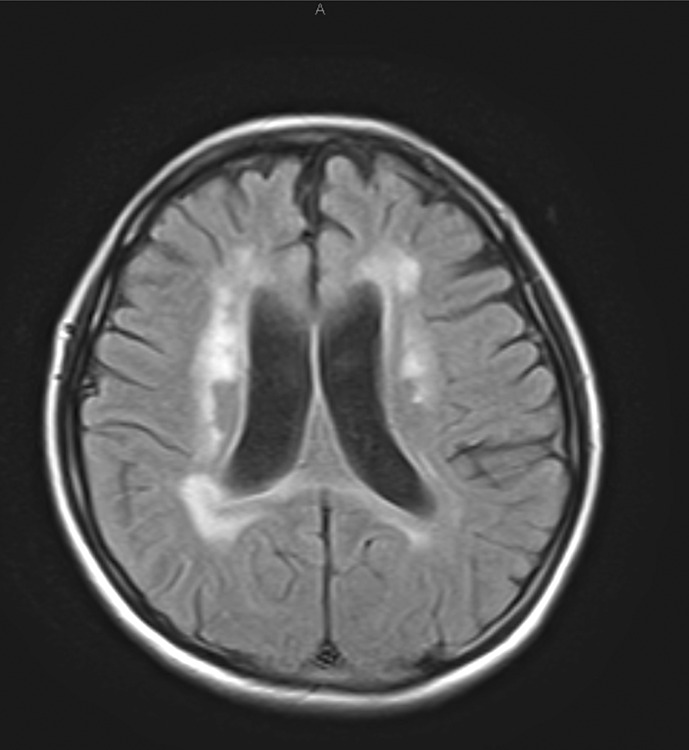

Case presentation: Cerebral magnetic resonance imaging showed confluent fluid-attenuated inversion recovery hyperintensities in the periventricular and frontal deep white matter, with multiple spotty calcifications in the frontal white matter by cerebral CT. Genetic testing revealed a mutation in the colony-stimulating factor 1 receptor (CSF1R).